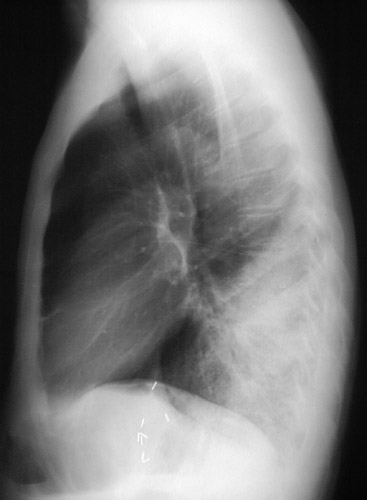

| The PA chest radiograph above demonstrates areas of opacification occupying the lower portion of the right lower lobe. The lateral view below reveals the infiltrates in this same area as well, consistent with a bronchopneumonia from a bacterial infection. (The bright vascular clips are from a previous abdominal surgery.) |